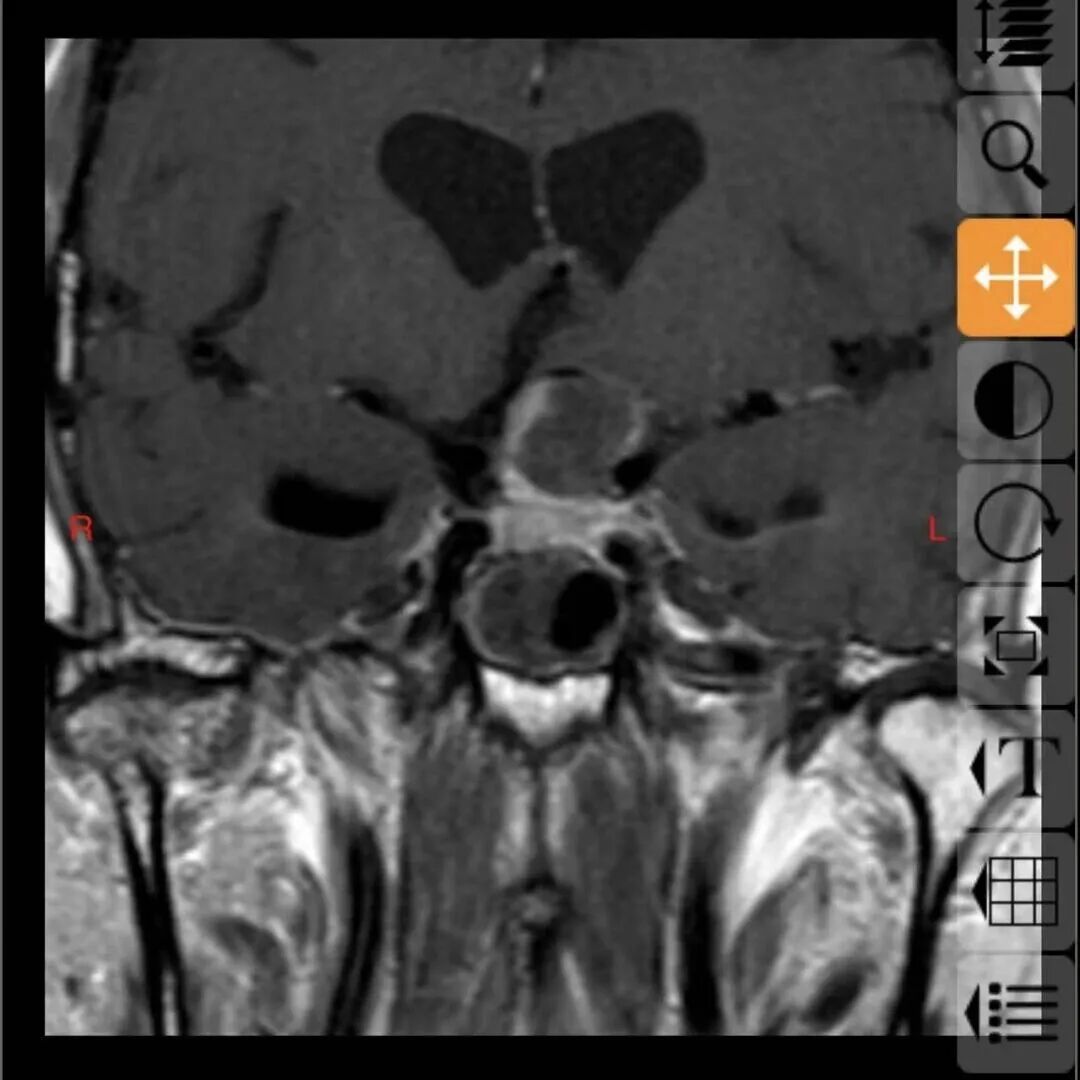

68岁的邓大叔是一位饱受垂体瘤困扰的“老战士”,11年前他经鼻行垂体瘤手术,几年后垂体瘤复发再次通过伽马刀治疗,经过两次历练后的他以为之后就可以高枕无忧,没想到近期的复查报告显示肿瘤“卷土重来”,且这次情况远比之前“棘手”,复发的肿瘤不仅从鞍内生长到鞍上,还与大脑的“生命线”——前交通动脉以及掌管意识记忆的三脑室底粘连紧密,甚至朝一侧颈内动脉上方生长,就像一颗埋在大脑深处的“不定时炸弹”,位置险要,结构复杂。

最终,由张治国主任主刀,为邓大叔顺利实施了这例高难度的经鼻蝶微创手术,肿瘤被完整、精准地切除,紧密粘连的前交通动脉及三脑室底均保护完好。